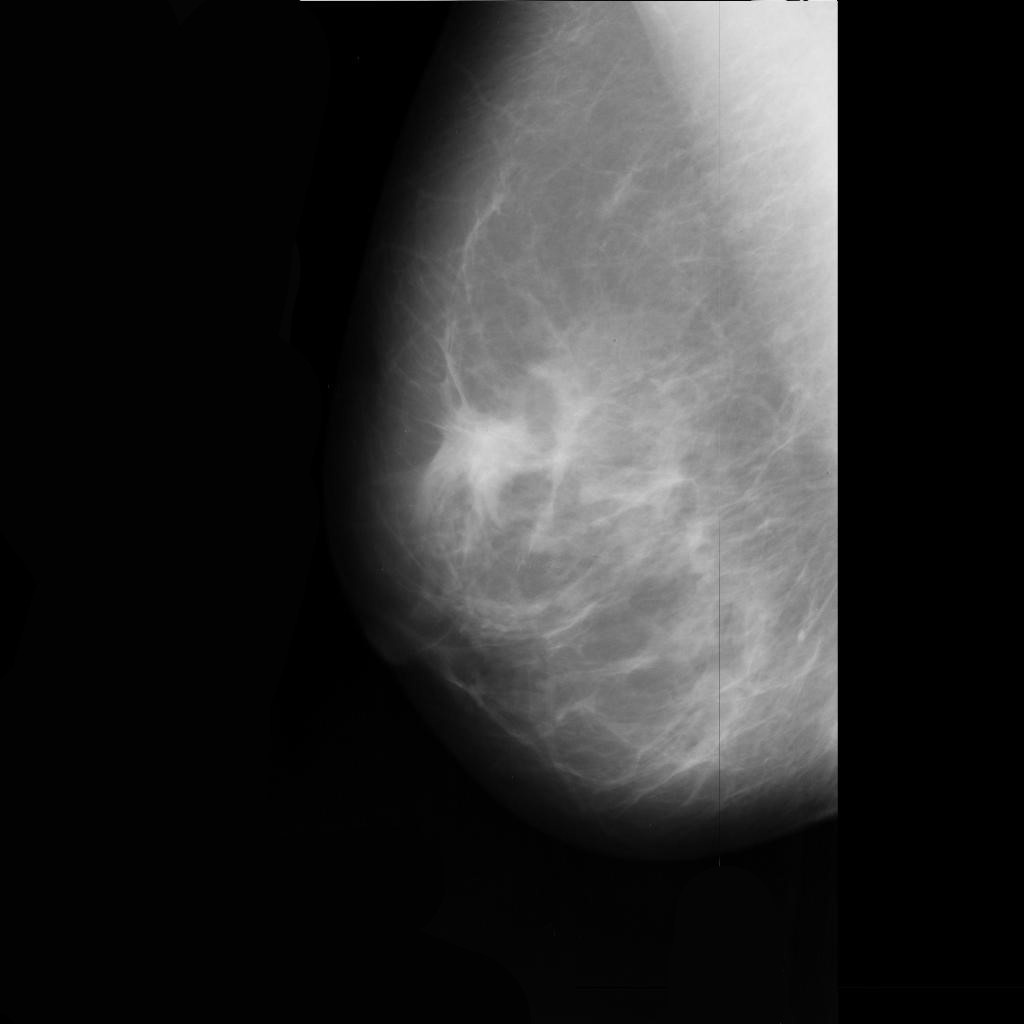

benign

malignant